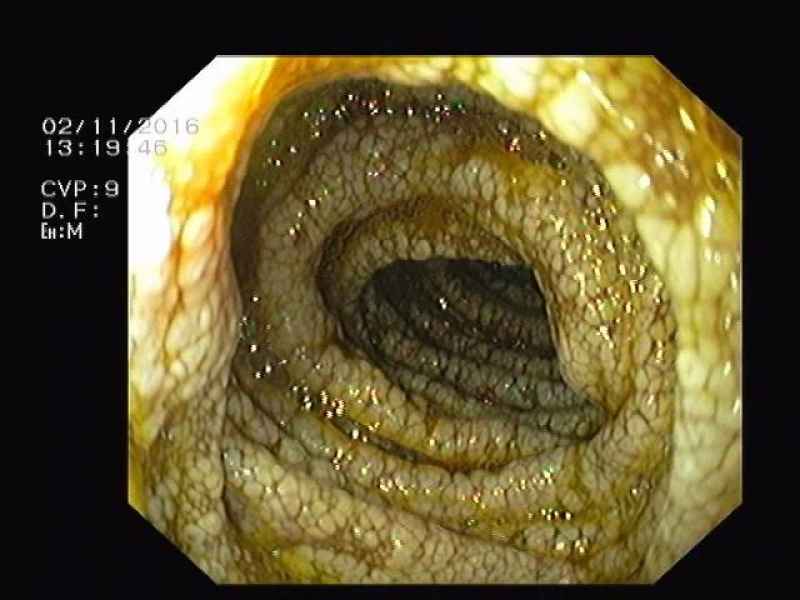

Diaphragm disease: Non-Steroidal Anti-Inflammatory Drug - Induced Enteropathy

Fotografia